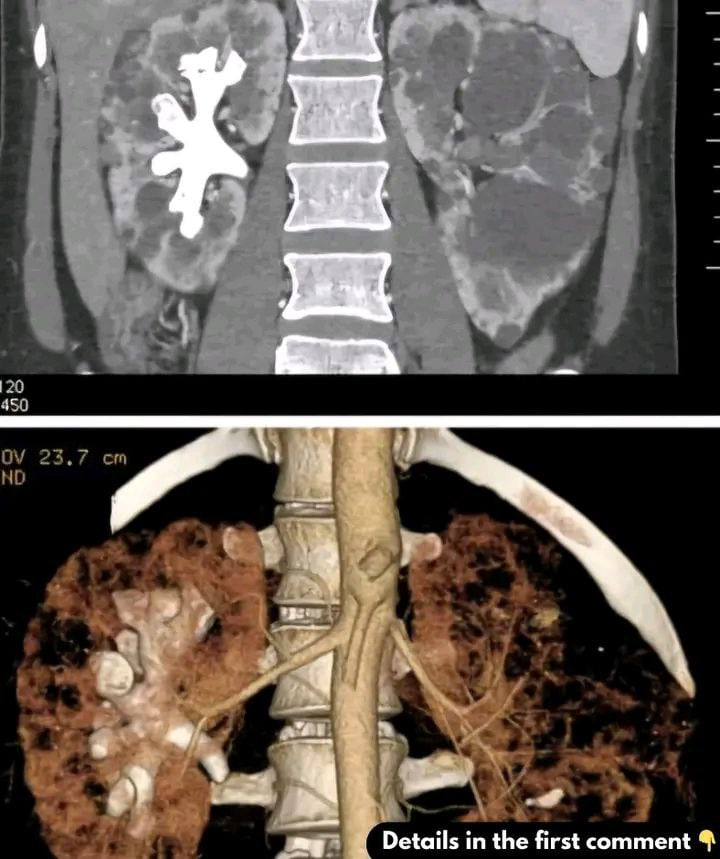

What Are Staghorn Kidney Stones?

Staghorn kidney stones are large, branching stones that occupy the renal pelvis and calyces of the kidney. They are often made of magnesium ammonium phosphate (struvite) and usually result from recurrent urinary tract infections (UTIs), particularly from bacteria that produce urease. These stones are more common in women and require surgical treatment, unlike smaller stones that can pass naturally.

Diagnosis involves imaging tests like CT scans, X-rays, and ultrasounds, along with urine and blood tests. For bacterial infections, urine cultures help identify the cause.